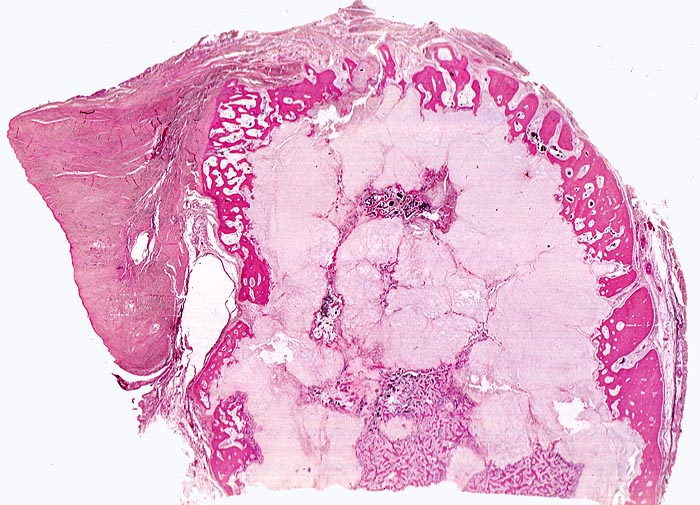

PathoPic ID 4518 - Chondrosarkom

Chondrosarkom

maligner Tumor

Knochen, Rippe

Knochen, Knorpel, Gelenke

In der Übersicht ist ein heller, zellarmer lobulierter Tumor erkennbar.

Zungenförmige Tumorausläufer infiltrieren die angrenzende Kortikalis.

Umschriebene Schmerzen im Bereich des Rippen-Thorax seit über einem Jahr.

Histologie

Scan

58

männlich